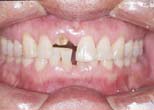

Forced eruption